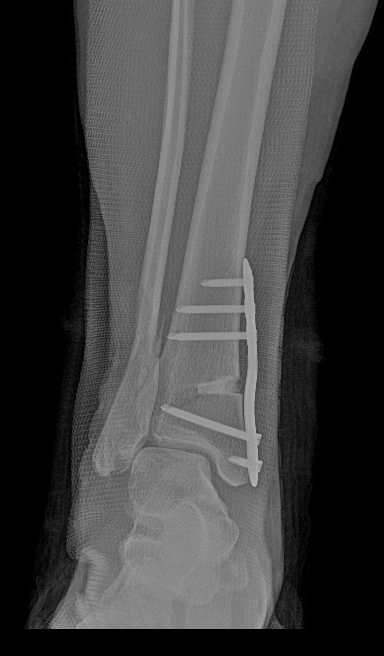

术后侧位X线

术后正位X线

武勇主任团队给他做了3D打印导板辅助下人工全踝关节置换术。

这种手术适合踝关节病严重的患者,通过替换病变的关节结构,能帮着缓解疼痛、恢复关节活动,让老人日常走路更自在些。